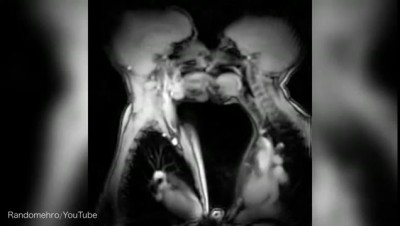

Sex-ray vision: Video reveals the inner workings of kissing and intercourse filmed using an MRI scanner The MRI scanner footage was compiled by news site Vox...

mri scans take a look at internal organs during sex